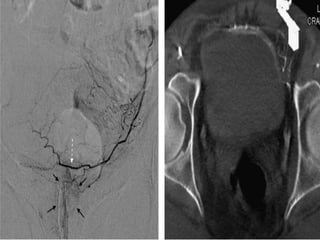

The prostate gland is a pyramid-shaped organ that weighs approximately 20 grams and measures 3x4x2 cm. It has three zones - the peripheral zone (70%), central zone (25%), and transitional zone (5-10%). Prostate cancer develops in the peripheral zone, while benign prostatic hyperplasia (BPH) develops in the transitional zone. The prostate receives its blood supply from various arteries, most commonly the internal pudendal artery (34%). Knowing the detailed arterial anatomy is important for procedures like prostate artery embolization (PAE) to treat conditions like BPH and prostate cancer. Imaging tools like CT angiography and cone beam CT can help the interventional radiologist map the arterial supply before